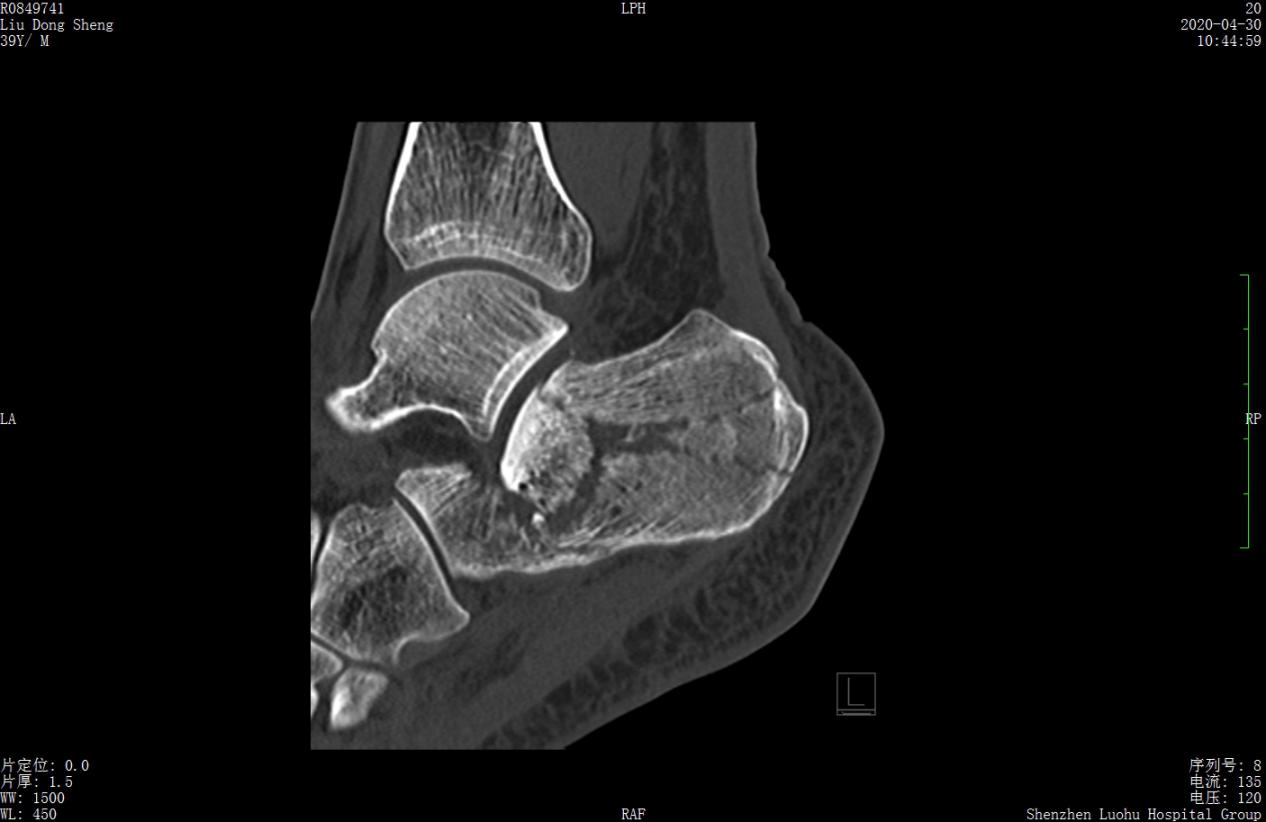

案例1影像

术前CT示跟骨严重粉碎骨折,移位明显